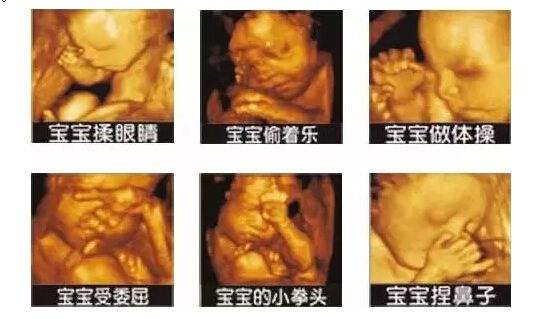

而彩超四維則是在三維的基礎(chǔ)上,加上了時間矢量,讓我們能在屏幕上清楚地看到,您未出生的寶寶實(shí)時動態(tài)活動圖像。我們可以看到寶寶的表情,再對寶寶進(jìn)行拍照,他們打哈欠、吃手指的照片就這樣保存下來了!